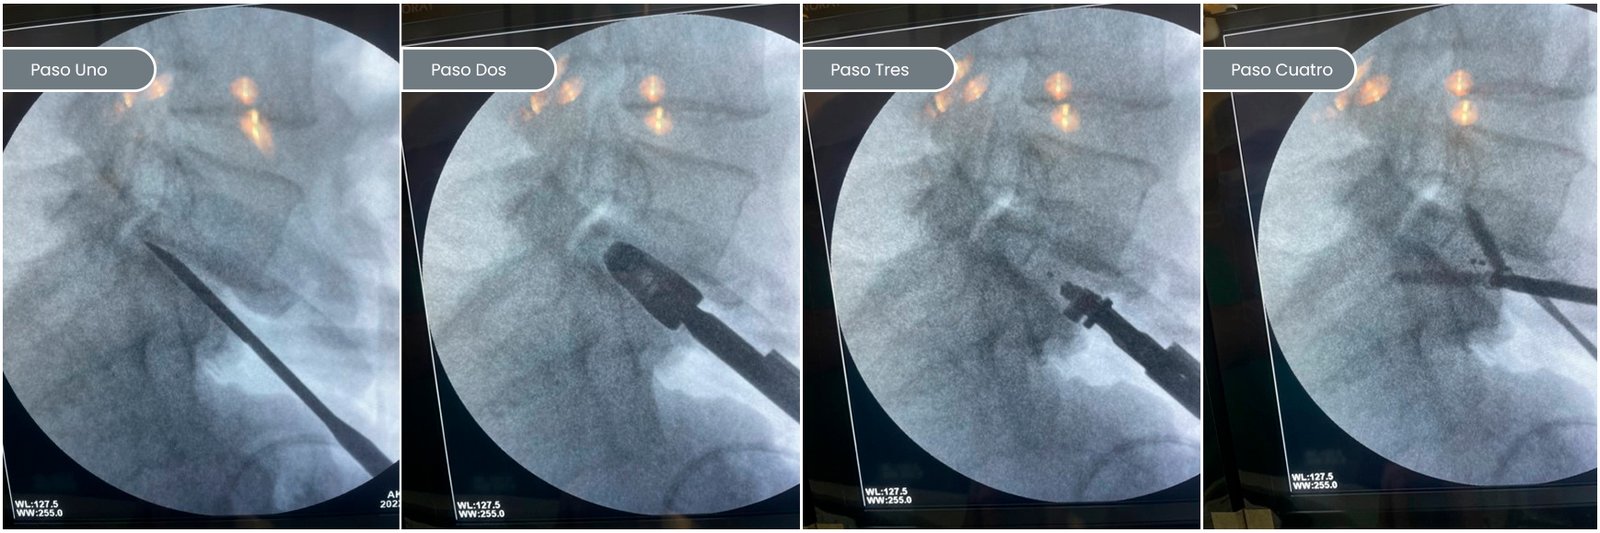

El bloqueo selectivo o infiltración consiste en realizar una inyección a nivel de la columna vertebral, a nivel de los espacios Inter discales, articulaciones facetarias y en las ventanas de salida (Neuro forámenes) de los nervios raquídeos afectados por hernias de disco o estrecheces que estén comprometiendo el normal recorrido de los mismos. Este procedimiento se utiliza comúnmente para el dolor lumbar crónico o ciática. Utilizamos para guiarnos, un equipo de imágenes de radioscopia. Son prácticas min invasivas cuyo objetivo es determinar: 1- Diagnóstico. Al inyectar el medicamento en un nervio o región específica, podemos determinar si esa área es la causa del dolor, lo que es valioso para guiar un tratamiento posterior o una intervención más específica. 2- Aliviar el dolor. Disminuir su intensidad nos permitirá poder comenzar con las terapias físicas para fortalecimiento (kinesiología). El procedimiento es ambulatorio (no requieren de internación), se realiza en el quirófano, ya que nos aseguramos con todas las normas de asepsia y esterilidad para su cuidado. El tiempo estimado de la práctica es de 20 minutos y se realizan bajo anestesia local (piel y planos profundos). Según cada caso, podemos aplicar lo que llamamos productos biológicos (Plasma rico en plaquetas, o cultivo de células adiposas) o utilizar Betametasona, esto se administra en altas concentraciones junto con anestésicos locales. El efecto del anestésico es aproximadamente 2 hs. Luego, puede reaparecer el dolor hasta que comiencen a actuar los otros medicamentos (PRP / Betametasona) entre las 24-48 hs. Este último tiene su máximo efecto entre los 10-15 días. Dependiendo de la enfermedad de base de su columna, el alivio puede ser permanente. Por lo general, le indicamos a los pacientes que durante las primeras 48 hs se debe hacer reposo relativo (no en cama, no hacer fuerza), colocarse hielo (20 minutos cada 3-4 horas por 24 hs), y si aparece algún dolor. Luego, de pasado ese descanso, el paciente puede comenzar actividades a las que venía haciendo antes del procedimiento. El día de la intervención, presentarse en ayuno e ir acompañado ya que recomendamos luego de la práctica no conducir o deambular.(ESTA ES LA SALA DE HEMODINAMIA DEL ICR, NUEVA, RECIEN ESTRENADA ESTE AÑO, MAXIMA TECNOLOGIA)

ALIF (ANTERIOR LUMBAR INTERBODY FUSION): EN ESTE PASO A PASO TE MUESTRO LA IMAGEN RADIOSCÓPICA DEL TRABAJO E INSTRUMENTACIÓN QUE VAMOS VIENDO HASTA TERMINAR CON LA CAJA COLOCADA